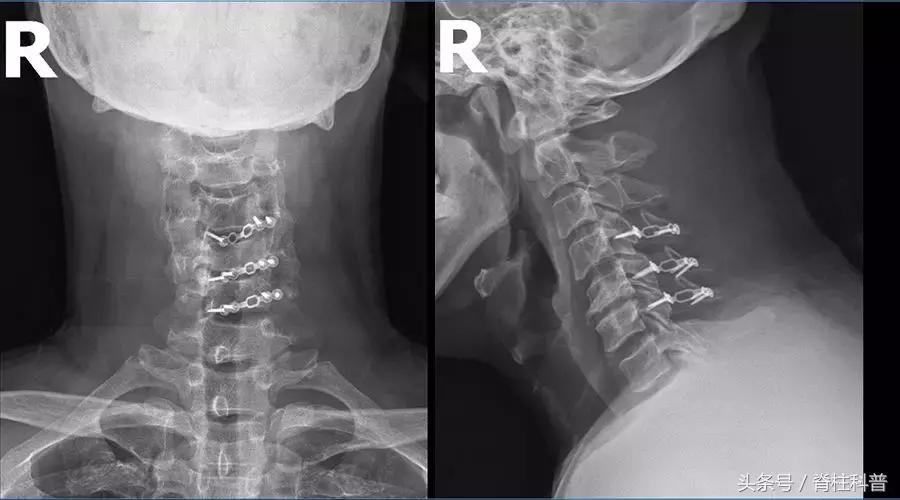

2018年6月19日被张忠民主任以“脊髓型颈椎病”收治入院。2018年6月24日,在气管插管全麻下做了减压和内固定的颈椎手术。(颈椎后路单开门式椎板成形术+ARCH钢板内固定术)